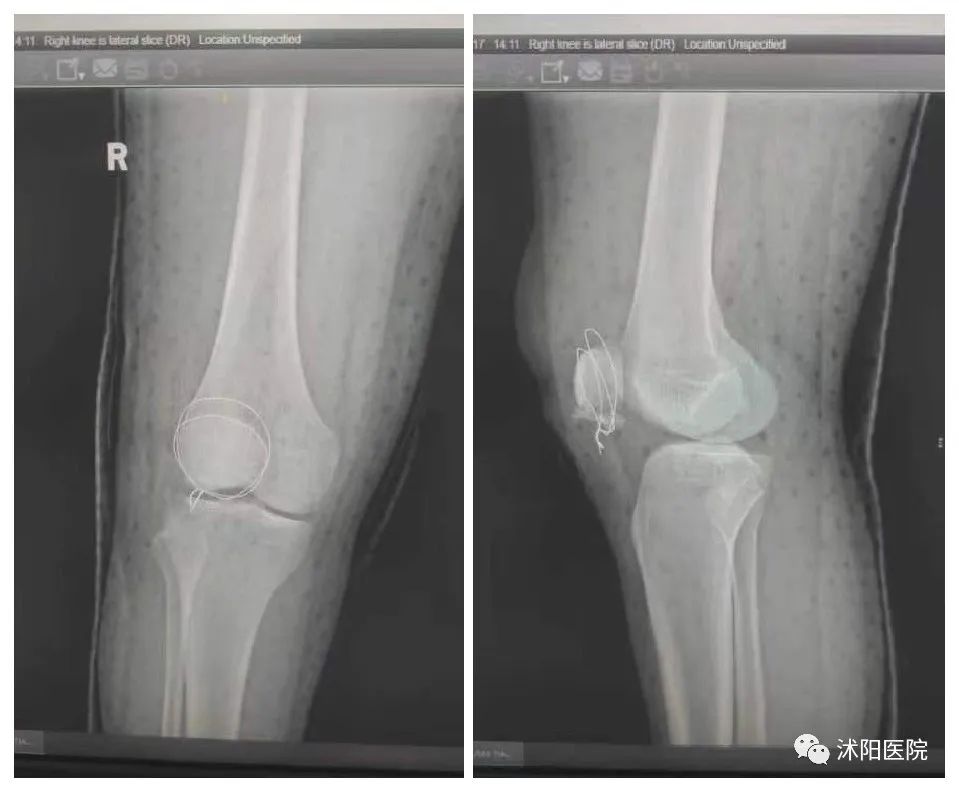

在为天赐进行临时石膏托固定,积极控制膝关节肿胀后,11月16日,祝振华主任带领小儿外科团队为患儿行右髌骨粉碎性骨折切开复位张力带钢丝内固定术。术中,祝振华主任将粉碎的髌骨一块一块进行了拼接整合,以张力带钢丝围绕髌骨周围一圈进行收紧缝合,用可吸收缝线缝合髌前韧带固定髌骨横裂。经过1小时10分钟的细心复位,手术顺利完成。术后摄片提示:骨折断端固定良好,髌骨外形恢复。

▲右髌骨骨折切开复位内固定术,张力带钢丝固定